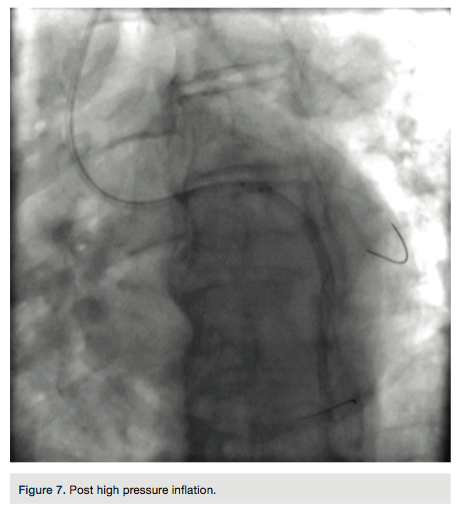

A 4 French (Fr) Glidesheath (Terumo Corporation) was inserted in the right radial artery and a vasodilator cocktail of 2.5 mg verapamil and 100 micrograms of nitroglycerin were given via the sheath. Since this was to be a planned chronic total occlusion (CTO) intervention, 5,000 units of heparin were given via an intravenous route. The 4 Fr introducer was exchanged out for a 6.5 PB4.0 Asahi sheathless guide (Asahi Intecc) (Figures 1-2). A control angiogram of the left coronary (Figure 3) reveals a total occlusion in the distal circumflex artery.

A Pilot 200 wire (Abbott Vascular) was loaded in a CrossBoss catheter (Boston Scientific) and advanced into the circumflex artery. The CrossBoss was slowly advanced, using the Pilot wire to redirect the device to remain as close to the lumen as possible. Once past the total obstruction, the Pilot 200 wire was used to re-enter the distal circumflex (Figures 3-4). A balloon dilation with a 1.5 mm x 20 mm long balloon was performed at 12 atmospheres (atm) followed by a 2.5 mm x 20mm balloon at 12 atm. A Runthrough wire (Terumo) was placed in the first marginal and stenting of the circumflex was performed using a 2.5 mm x 38 mm Promus Premier stent (Boston Scientific) overlapped with a 3.0 mm x 24 mm Promus Premier stent. High-pressure inflation in the entire stented segment was performed using a 3.0 mm balloon. The segment proximal to the first obtuse marginal was dilated to high pressure using a 3.25 mm balloon (Figures 5-7). A good angiographic result was seen (Figure 8).